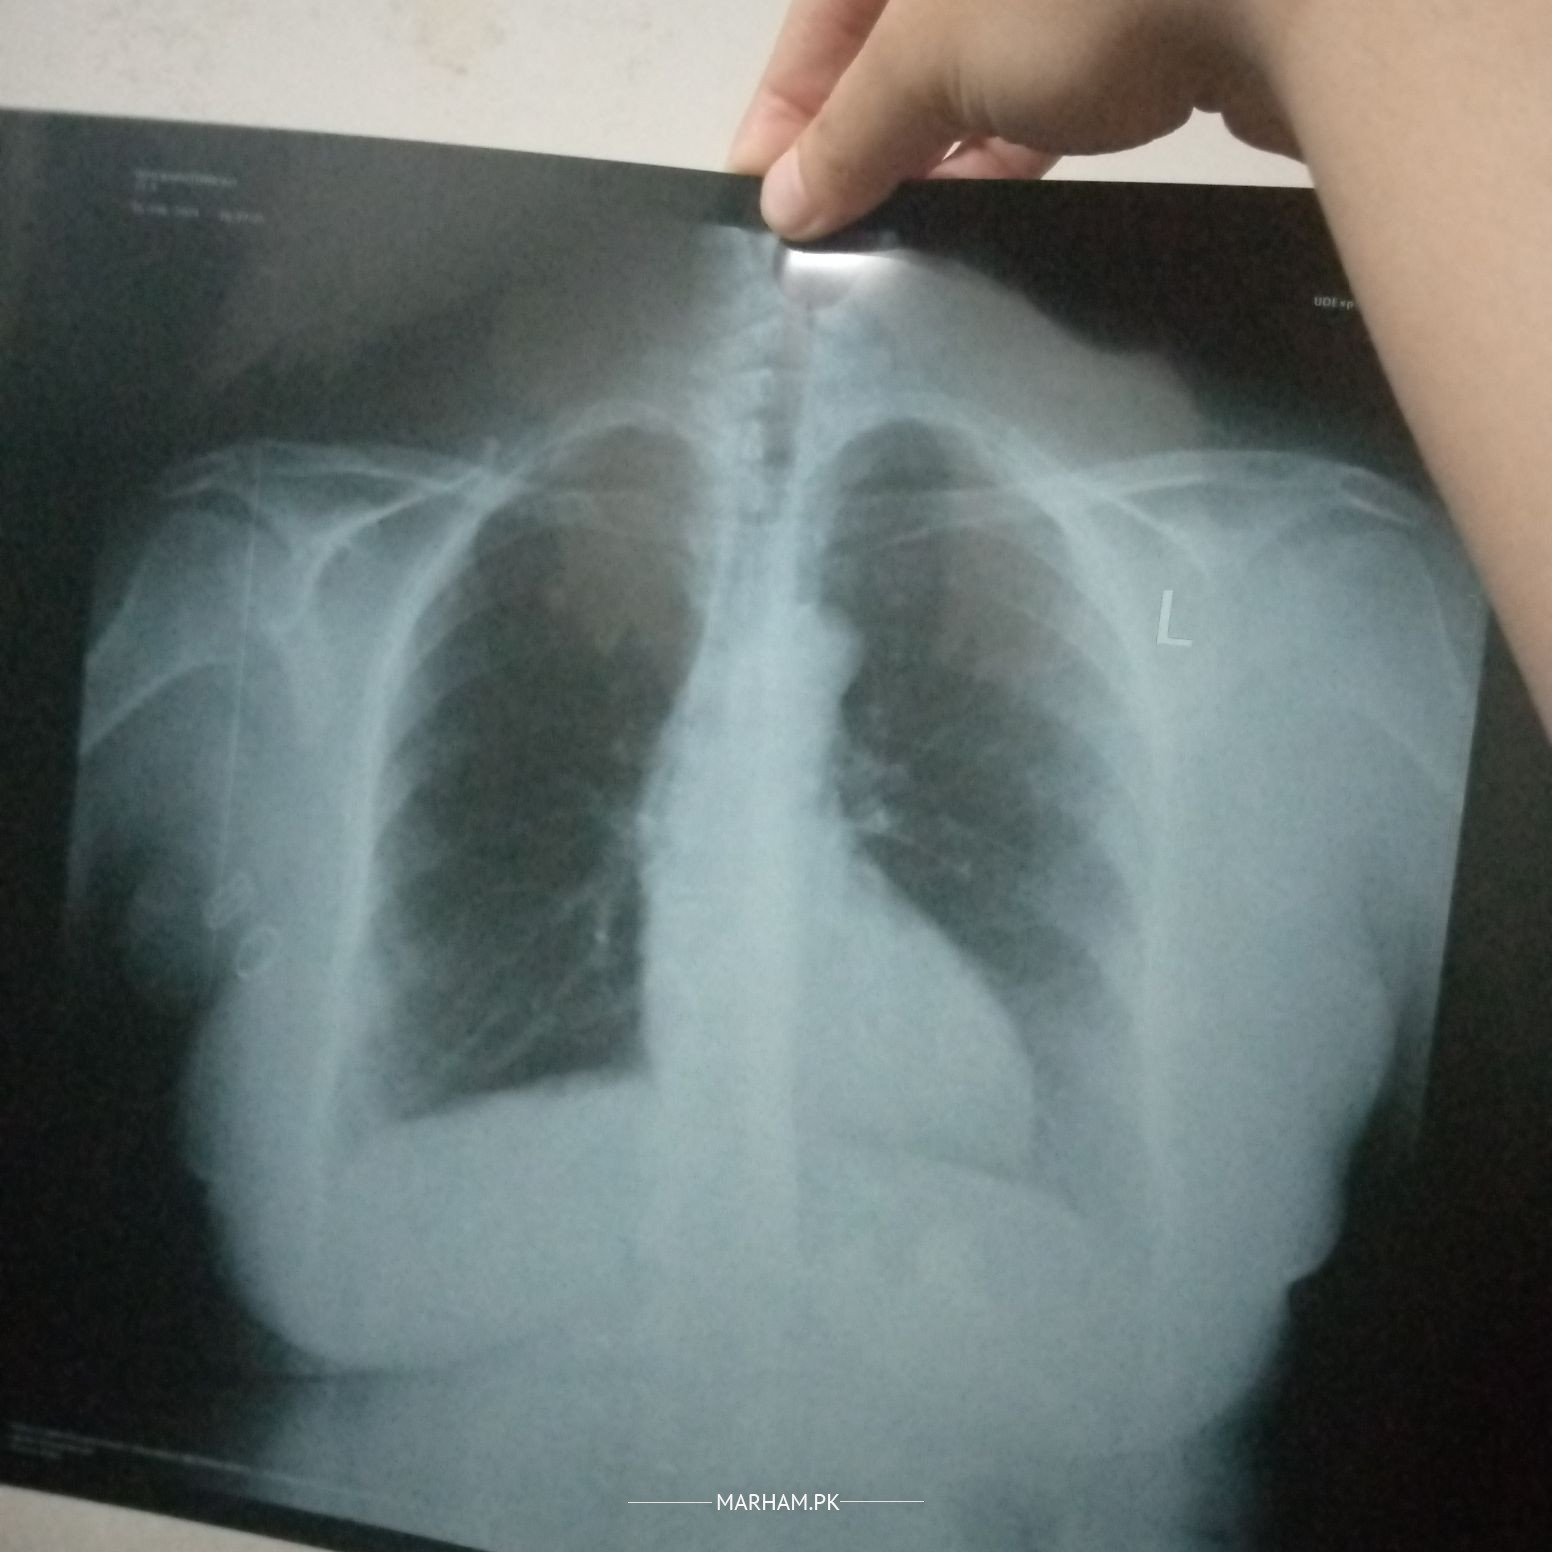

send me photo again and also x ray reports

X-ray report